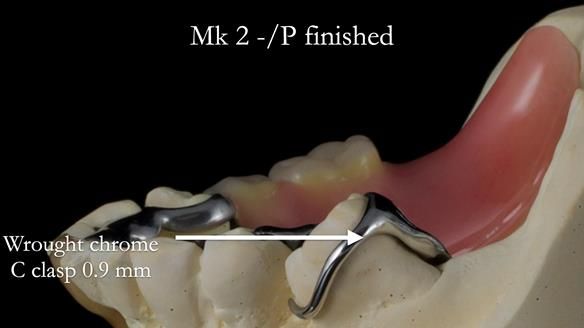

Welcome to my Newsletter 54 showing the making and fitting of dentures (a complete upper metal reinforced denture, a lower immediate partial denture and a definitive Scandinavian designed, metal based lower partial denture) for David, a 75 -year-old man. The full protocol workflow is presented including the use of dentate photographs to mimic his natural teeth.

The clinical situation and treatment process is shown in detail below. I provided the clinical work. Rowan Garstang, my dental technician, provided the technical work.

Interestingly we found that the upper complete denture when finished and fitted didn’t have good enough retention for David’s satisfaction. It was relined by adding compound to the buccal flanges – to almost overextend into the sulcus to ‘create’ a sulcus, followed by using a light bodied silicone impression material. This improved the function of the C/-considerably. A lower Scandinavian hygienically designed lower RPD was also provided which helped with occlusal stability and reseating the upper denture – further improving the fit.